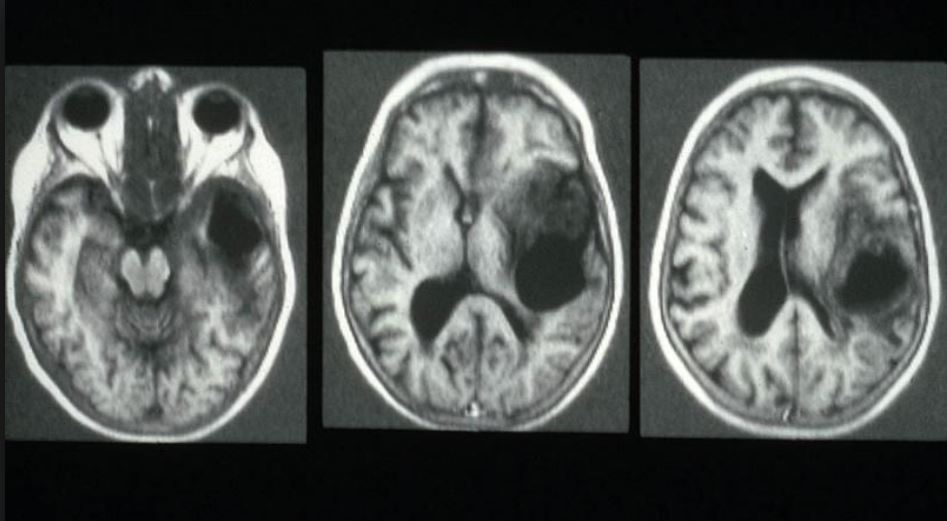

Что такое фокальная корковая дисплазия височной доли